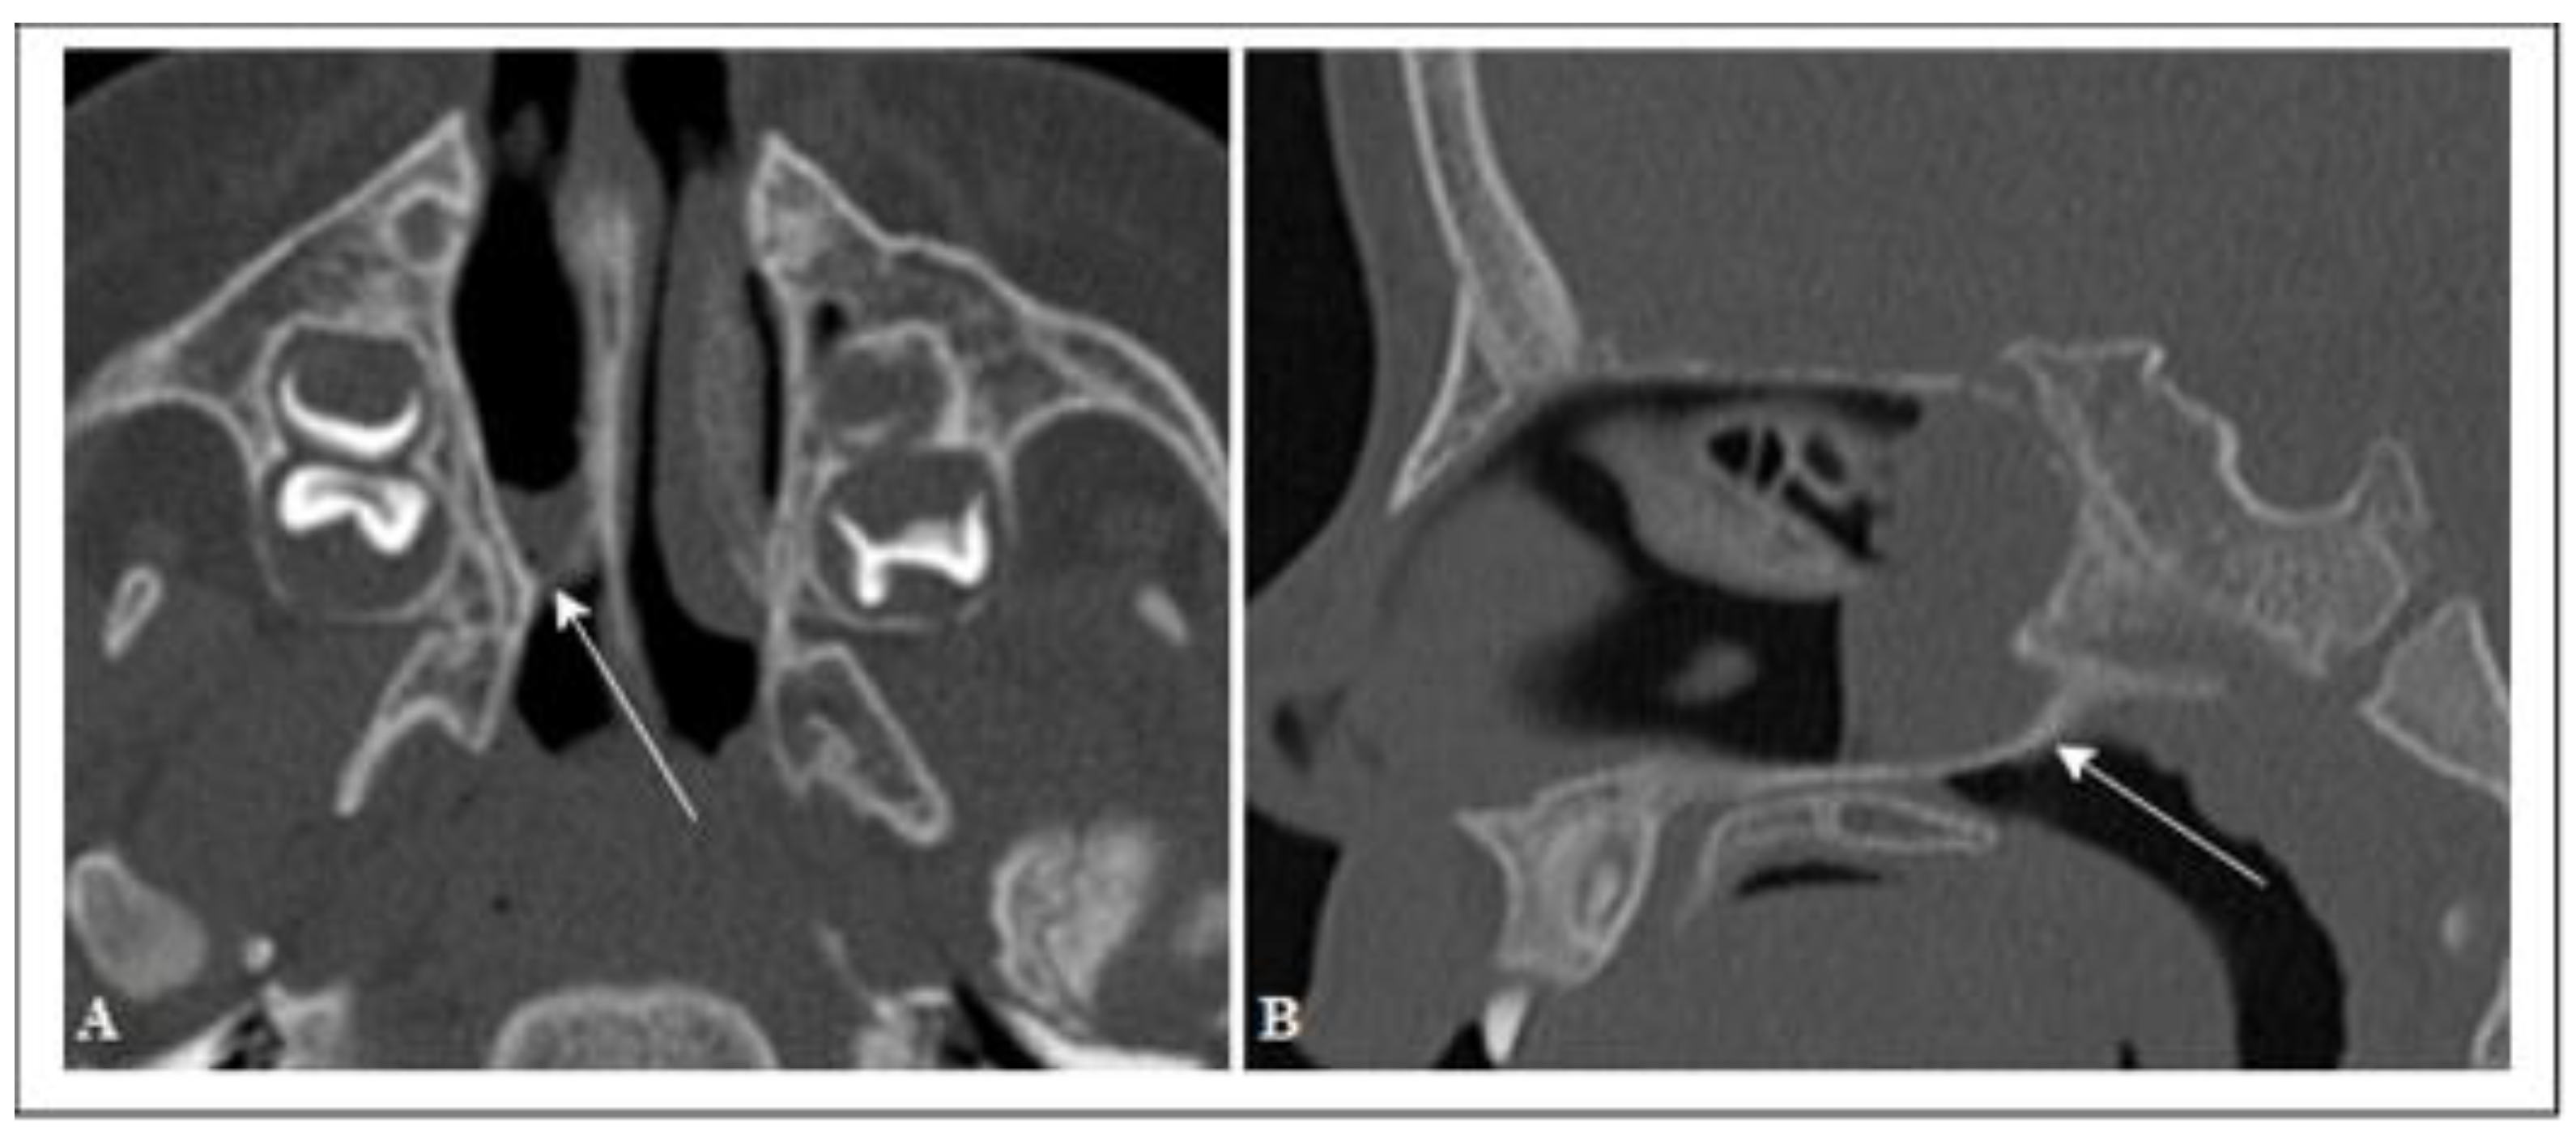

| Choanal height (CH) | The distance between the horizontal lamina of the palatine bone and the body of the sphenoid |

| Rostrum height (RH) | The distance between the body of the sphenoid and the junction point of the vomer wings |